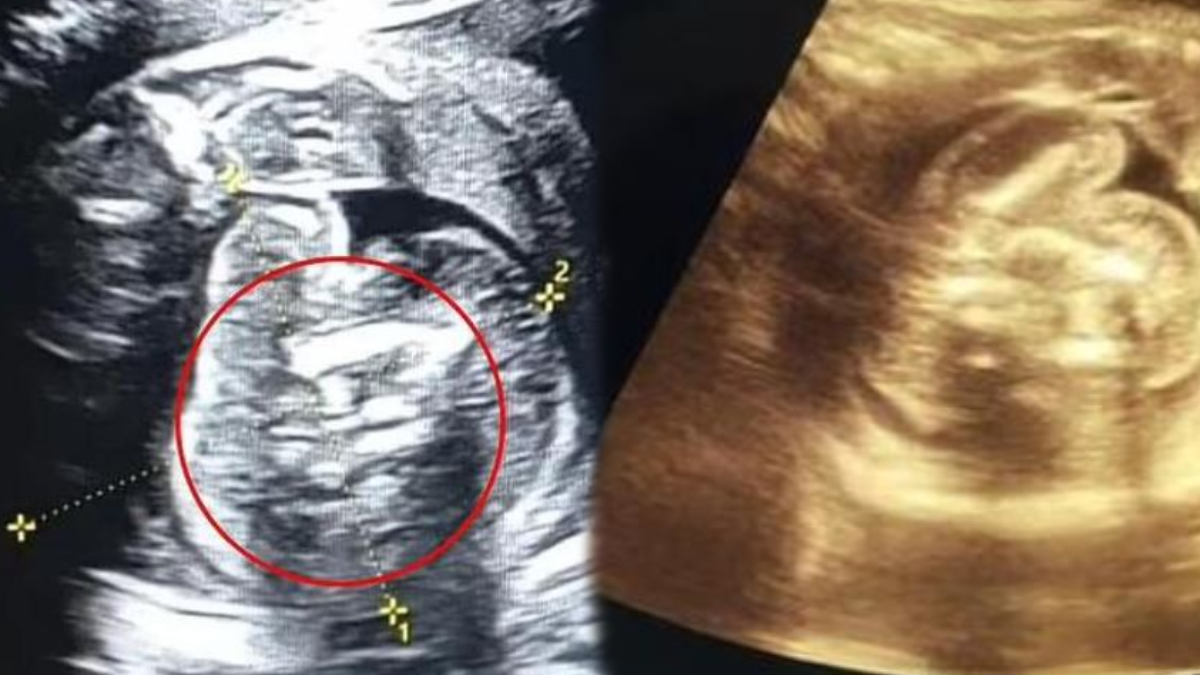

25 haftalık hamileliği sonrası rutin tarama için yerel bir hastaneyi ziyaret eden kadının doğmamış bebeğin karnında doktorlar, 'kemik içeren ek bir yapı' keşfedildi. Yapılan tetikler sonucunda fetüsün karnında 2 tane daha şekil bozukluğu olduğu ortaya çıktı.

Taramayı gerçekleştiren Dr. Prasad Agarwal yaşanılan durumla ilgili, "Bu bebekte çok sıra dışı bir şey fark edecek kadar şanslı ve dikkatliydim. Birkaç kemiği ve karnında fetüs benzeri bir yapı bulunan, son derece normal büyüyen bir fetüs." dedi.

Yaşanılanın normal olmadığını aktaran doktor, "Bu, dünyadaki en nadir vakalardan biri olan 'fetüs içinde fetüs'." diye konuştu.